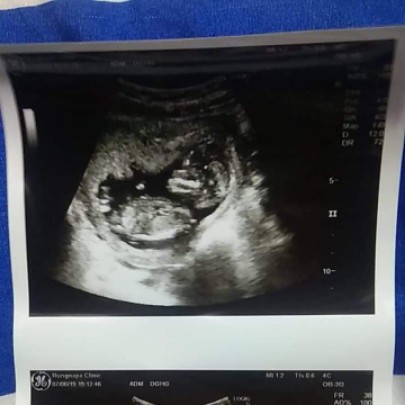

12w4d

Post reply image